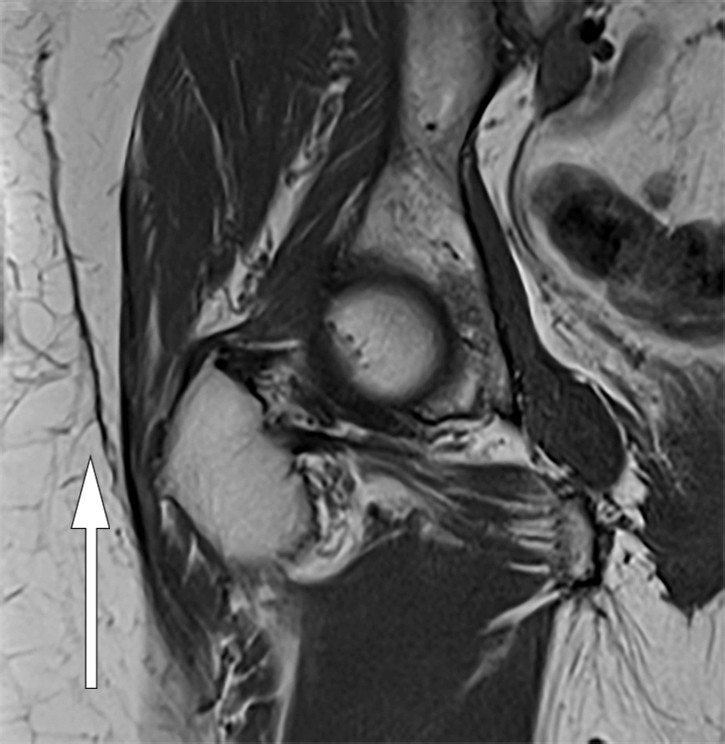

Eleven months after the trauma, the patient experienced another recurrence, and pelvic MRI revealed an unchanged subcutaneous locule. The radiologist suspected a Morel-Lavallée lesion (Figure 1). It was decided to perform an elective open excision of the locule, including the capsule, with primary suturing in the operating theatre. One week after the excision, the patient experienced another recurrence. A further aspiration was performed and compression attempted in the outpatient clinic, but without success.

Figure 1 Coronal T1-weighted MRI of right hip. Well-defined, elongated, lenticular structure with homogeneous intermediate…

Figure 1 Coronal T1-weighted MRI of right hip. Well-defined, elongated, lenticular structure with homogeneous intermediate signal located over the deep fascia.